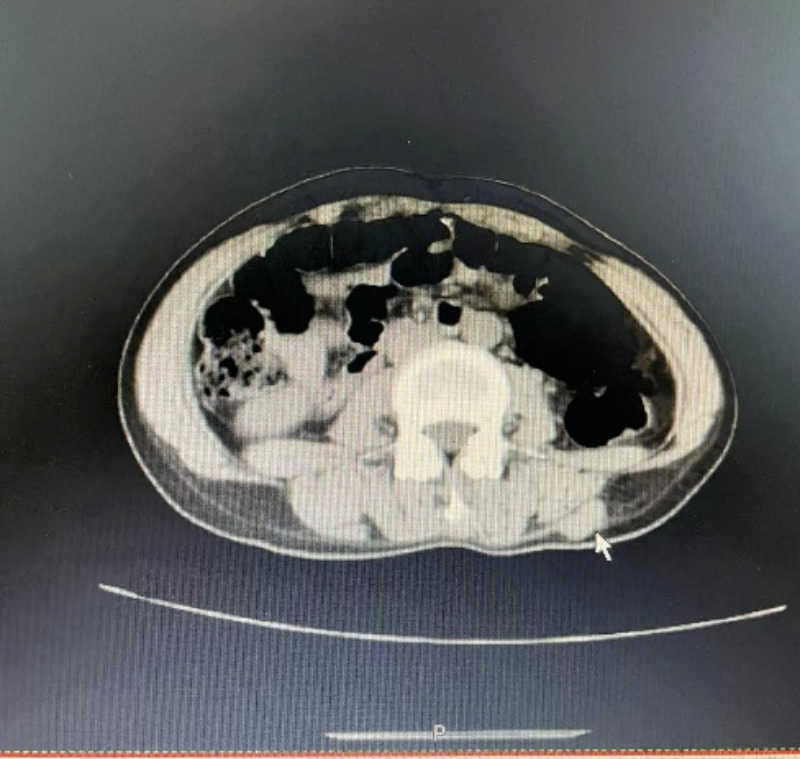

介入灌注化療后。

從影像中可以看出,之前因腫瘤直徑太大而無法切除,現通過介入灌注化療+靶向治療+免疫治療后,肝內病灶已基本無活性,后續可以進行手術切除腫瘤。

冷凍消融中。